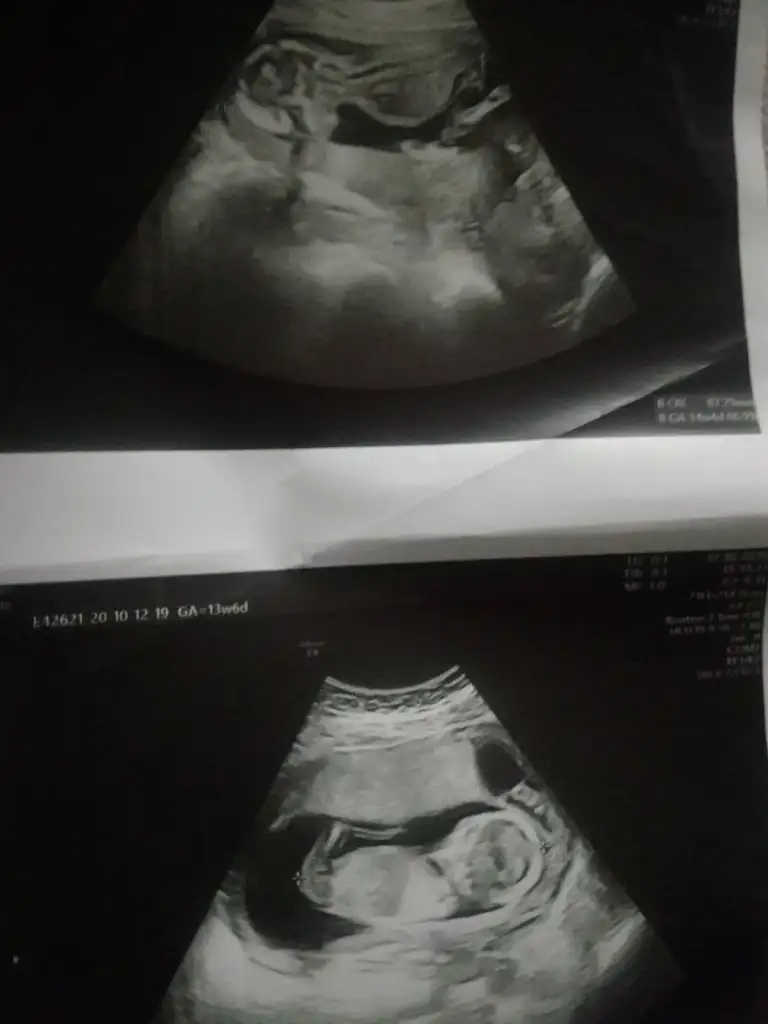

Teşekkür ederim canımKız gibi sanki 14 haftada nub olmaz ama sanki diklik olsa yada pipi olsa görünürdüolmayada bilir

Altaki kız üsteki erkek sanki onun nubu yarım görünüyor biraz dik gibi geldi bana

Yaa bnada böyle geliyorAltaki kız üsteki erkek sanki onun nubu yarım görünüyor biraz dik gibi geldi banabaşka USG varsa paylaşın

Evet ikisi kız gibi sankiAmin ininşaallahvalla hiç poz vermediler hep kapattılar ama doktor ikisinde de çengel falan dedi sanırım cinsiyet kısımları bunlar ben hiç bişey anlamıyorum ama attım bugün tam 14hafta bitti